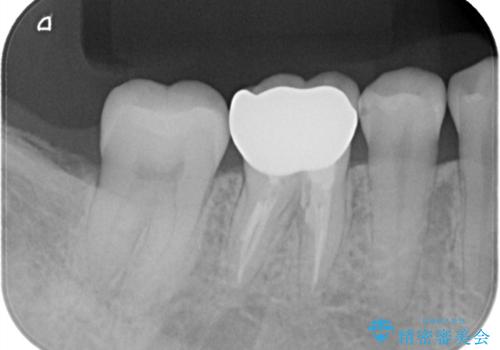

根管内を見てみると、近心根は本来の根管とは違うところを削られて髄床底でパーフォレーションを起こしていました。

また、遠心根でも本来の根管とは逸脱した方向に根管形成されていましたが、修正し充填を行っています。

パーフォレーション部位に関しては、口腔内との交通がなければMTAセメントを用いて修復することで、高い予知性を期待できます。